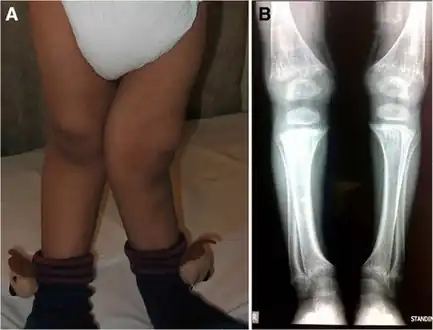

There (are) three distinct types of cystinosis each with slightly different symptoms: nephropathic cystinosis, intermediate cystinosis, and non-nephropathic or ocular cystinosis. Infants affected by nephropathic cystinosis initially exhibit poor growth and particular kidney problems (sometimes called renal Fanconi syndrome). The kidney problems lead to the loss of important minerals, salts, fluids, and other nutrients. The loss of nutrients not only impairs growth, but may result in soft, bowed bones (hypophosphatemic rickets), especially in the legs. The nutrient imbalances in the body lead to increased urination, thirst, dehydration, and abnormally acidic blood (acidosis).

Rickets in cystinosis. a- A cystinosis child with evident rachitic bone deformities. b- Active rachitic bone disease in X-Rays